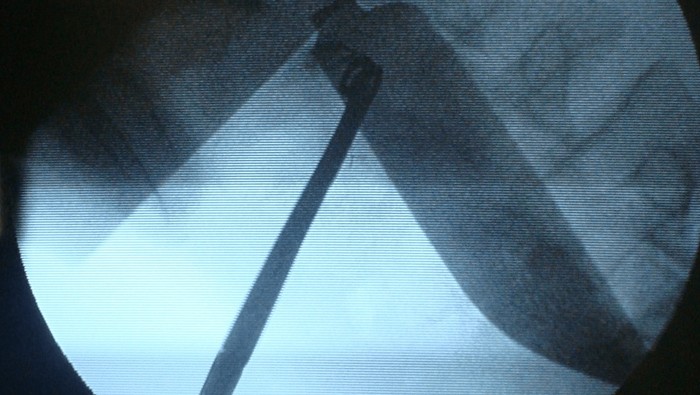

Pasien kemudian dibawa ke ruang operasi dan pencitraan diulang di bawah fluoroskopi, yang mengungkapkan lokasi bilah pisau di dalam rongga perut. Laparotomi dilakukan, dan bilah pisau sepanjang 15 cm ditemukan di daerah iliaka kirinya. Untungnya, tidak ada cedera parah pada organ-organ di sekitarnya. (Foto: Jurnal Cureus).